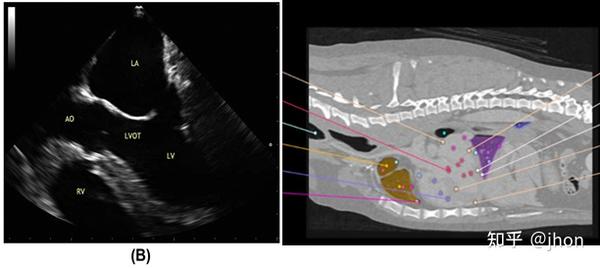

超声心动图,超声心动图怎么做

疑似主动脉瓣脱垂的主动脉夹层超声心动图诊断分析

超声心动图切面图解